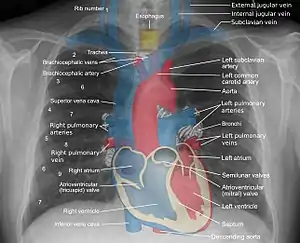

The mediastinum can be seen from a frontal view in this illustration, with the superior mediastinum labeled a, and the pericardial cavity, which is part of the inferior mediastinum, labeled d.

Mediastinum anatomy.

Some mediastinal structures on a chest radiograph.